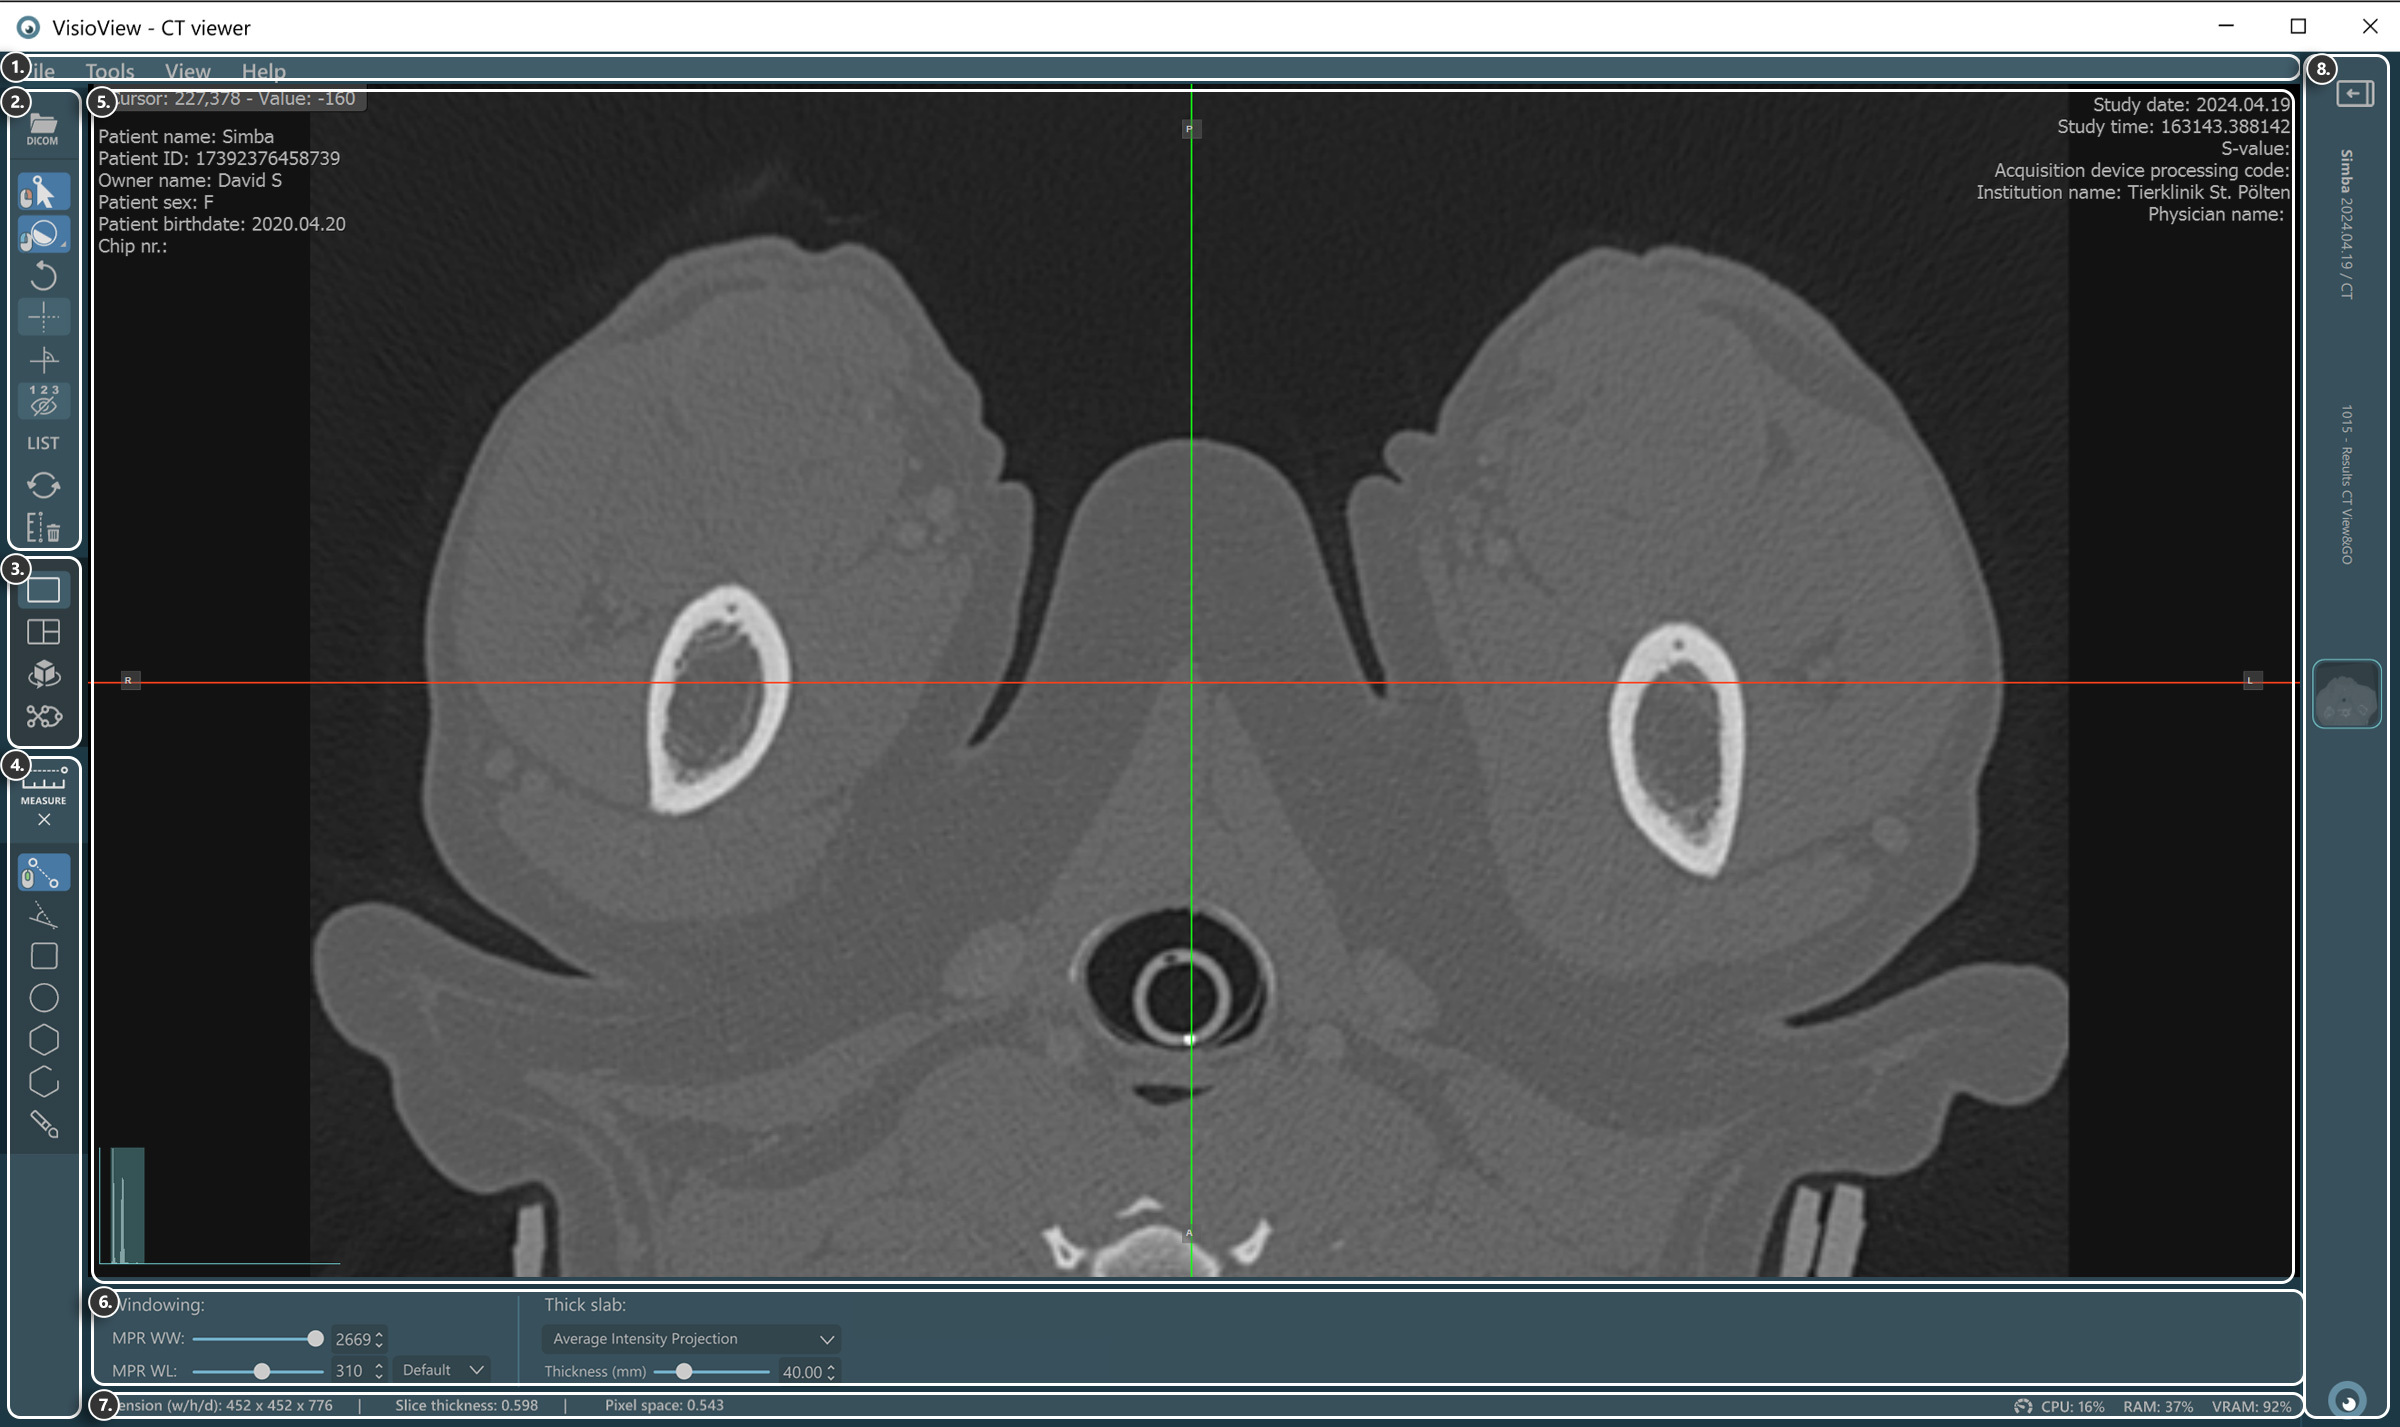

Sections of the VisioVIEW CT Viewer

The VisioVIEW CT Viewer consists of several sections, each tailored to a specific purpose. Below is a detailed description of each section.

../_images/image121.jpg

1. Menu Bar

2. Tools and Options

3. View Selector

4. Measurement Tools

5. Viewer Area

6. View Settings and Options

7. Information Bar

8. Study Information & Series Panel